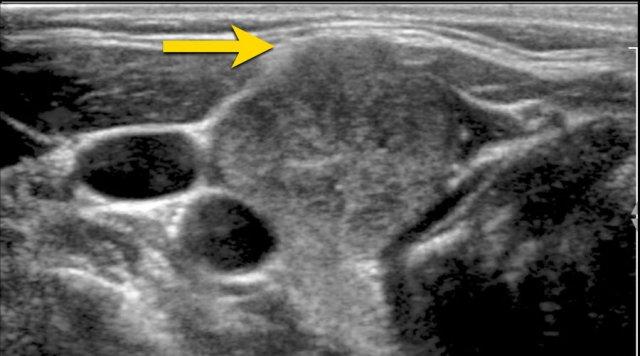

Nốt với Bờ Không Đều, Có Múi

Hình ảnh cho thấy bờ không đều, có múi ở mặt trước của nốt.

Điểm TI-RADS: 2 điểm.